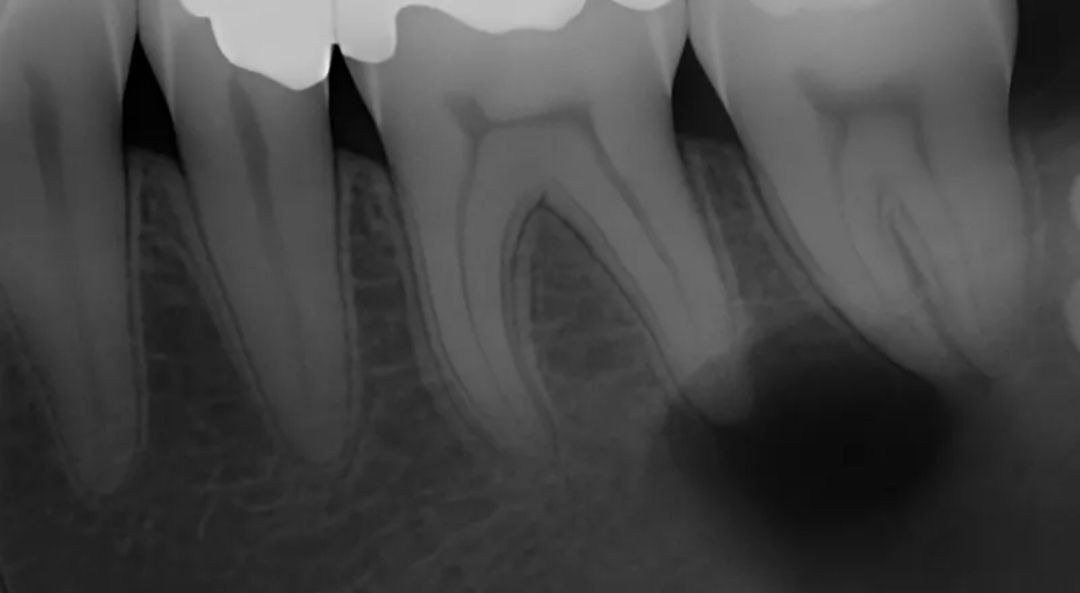

Киста

Киста под зубом — это доброкачественное образование в костной ткани челюсти, заполненное жидкостью. Она образуется у верхушки корня зуба как защитная реакция организма на инфекцию.

Основная причина: инфекция попадает в корневые каналы (через невылеченный кариес, пульпит, травму) и организм отделяет очаг воспаления плотной капсулой.

Долгое время киста развивается бессимптомно

Киста постепенно разрушает кость, может привести потере зуба или распространению инфекции в другие органы и ткани.